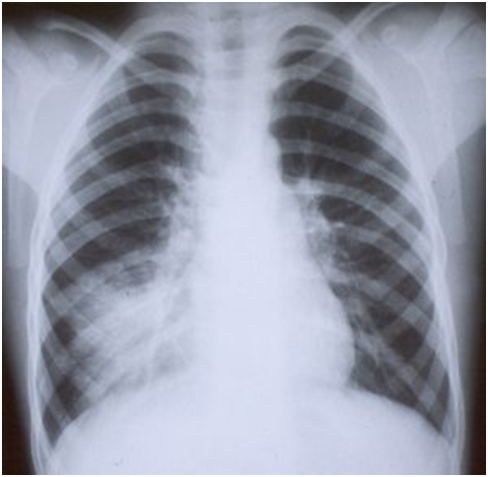

Rx de Tórax

Raio-X de pneumonia lobar (lobo superior)

Raio-X de pneumonia lobar (lobo médio)

Raio-X de pneumonia intersticial